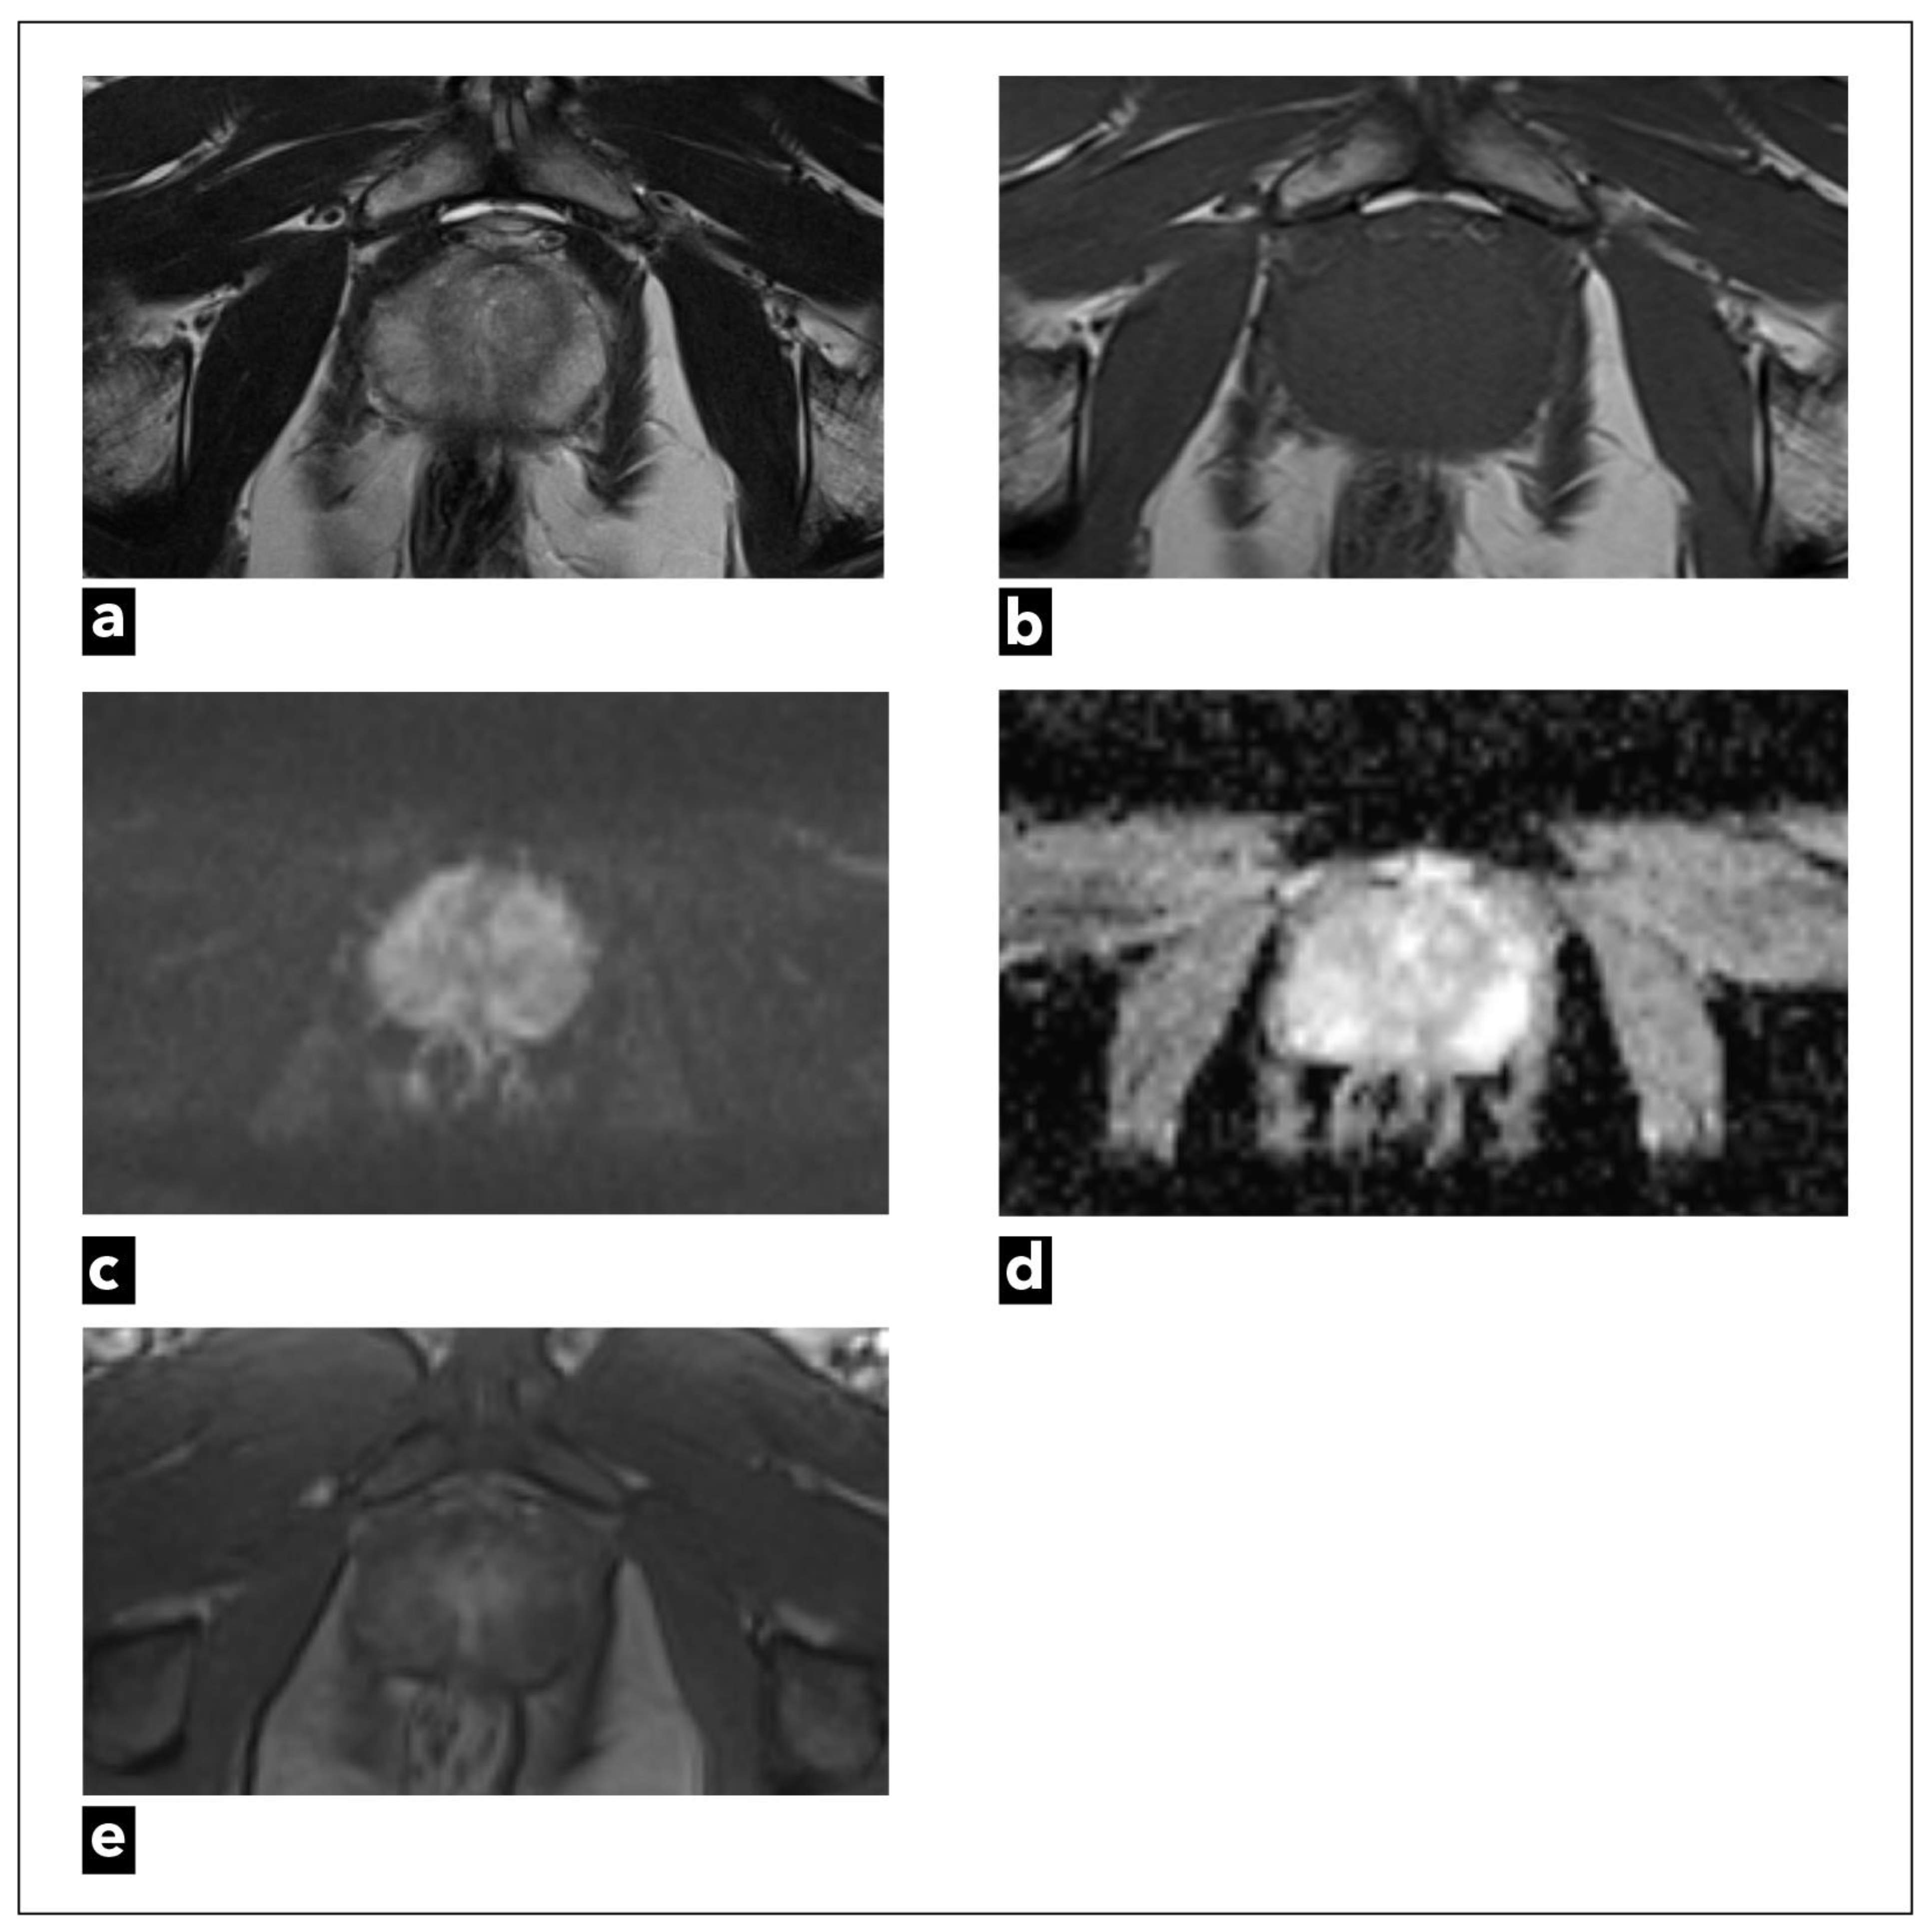

They suggest dividing patients into three categories: low, intermediate, and high risk, and using DCE-MRI in intermediate and high-risk patients. However, when it comes to low-risk group patients, such as patients undergoing screening where there is a higher risk of overdiagnosing, the committee regards bpMRI as a potentially reasonable method [133]. Examinations categorised as PI-RADS 1 or 2 can be scored using only T2W sequence and DWI, which can also be used in the majority of highly suspicious examinations, especially those categorised as PI-RADS 5 (Figure 7). DCE-MRI can have a crucial role when it comes to small cancers, cancers that are found in locations that may be more difficult to analyse with T2W or DWI sequences, like the apex of the prostate, the subcapsular area of both the peripheral and central zones, or when T2W and DWI are of suboptimal diagnostic quality (Figure 8) [134].

Also, using DCE-MRI has been proven very useful to less experienced radiologists, helping them to find less obvious prostate cancers with more confidence [135]. When it comes to more experienced readers, studies have shown an increment in the number of indeterminate cases in bpMRI examinations, both for PI-RADS and Likert categorisations [119,136]. Implementing bpMRI in everyday clinical practice would require some adjustments and strict guidelines on when to use contrast. It is essential to have high-quality T2W and DWI sequences, reading radiologists with sufficient experience, and validate biopsy decisions in correlation with clinical risk for prostate cancer. In indeterminate cases or cases with suboptimal quality of T2W and DWI sequences, patients should be recalled for additional DCE-MRI sequences [133]. Recalling patients can result in a new problem of delayed diagnosis and can be a complication for some patients.